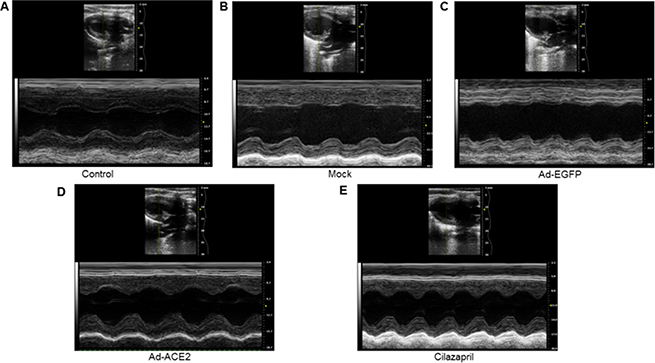

Echocardiographic measurements

As shown in Figure 6 and Table 1, LV end-systolic diameter and LVEDD were significantly decreased, whereas LVEF and FS were increased in the Ad-ACE2 and Cilazapril groups in comparison with the Mock and Ad-EGFP groups. In addition, LVEDD were higher, whereas LVEF and FS were lower in the Cilazapril group than in the Ad-ACE2 group. However, ACE2 and cilazapril had no significant effect on blood pressure and heart rate in doxorubicin-induced cardiomyopathy rats (Table 1).

Figure 6: Cardiac function data in five groups of rats 4 weeks after gene transfer. Representative echocardiographic graphs in 2D parasternal long axis view and M-mode of the left ventricle (LV) at the level of the papillary muscles. N is 8–15 in each group.